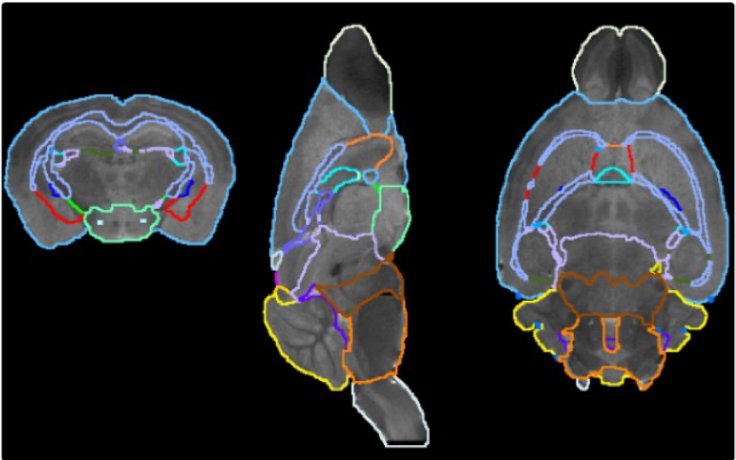

pmod’s tools provide comprehensive workflows for post-processing and quantification of imaging data for fundamental oncology research, development of radiotracers and theranostics, and in clinical research studies. Imaging scientists can trust pmod to reproducibly read their data, interpret the meta-data/units and help users calculate statistics such as SUV for their studies and publications.

• Multimodality segmentation tools – comprehensive semi-automated and manual tools for precision and reproducibility

• Full access to metadata – ensure accurate calculation of Standard Uptake Value and other key statistics